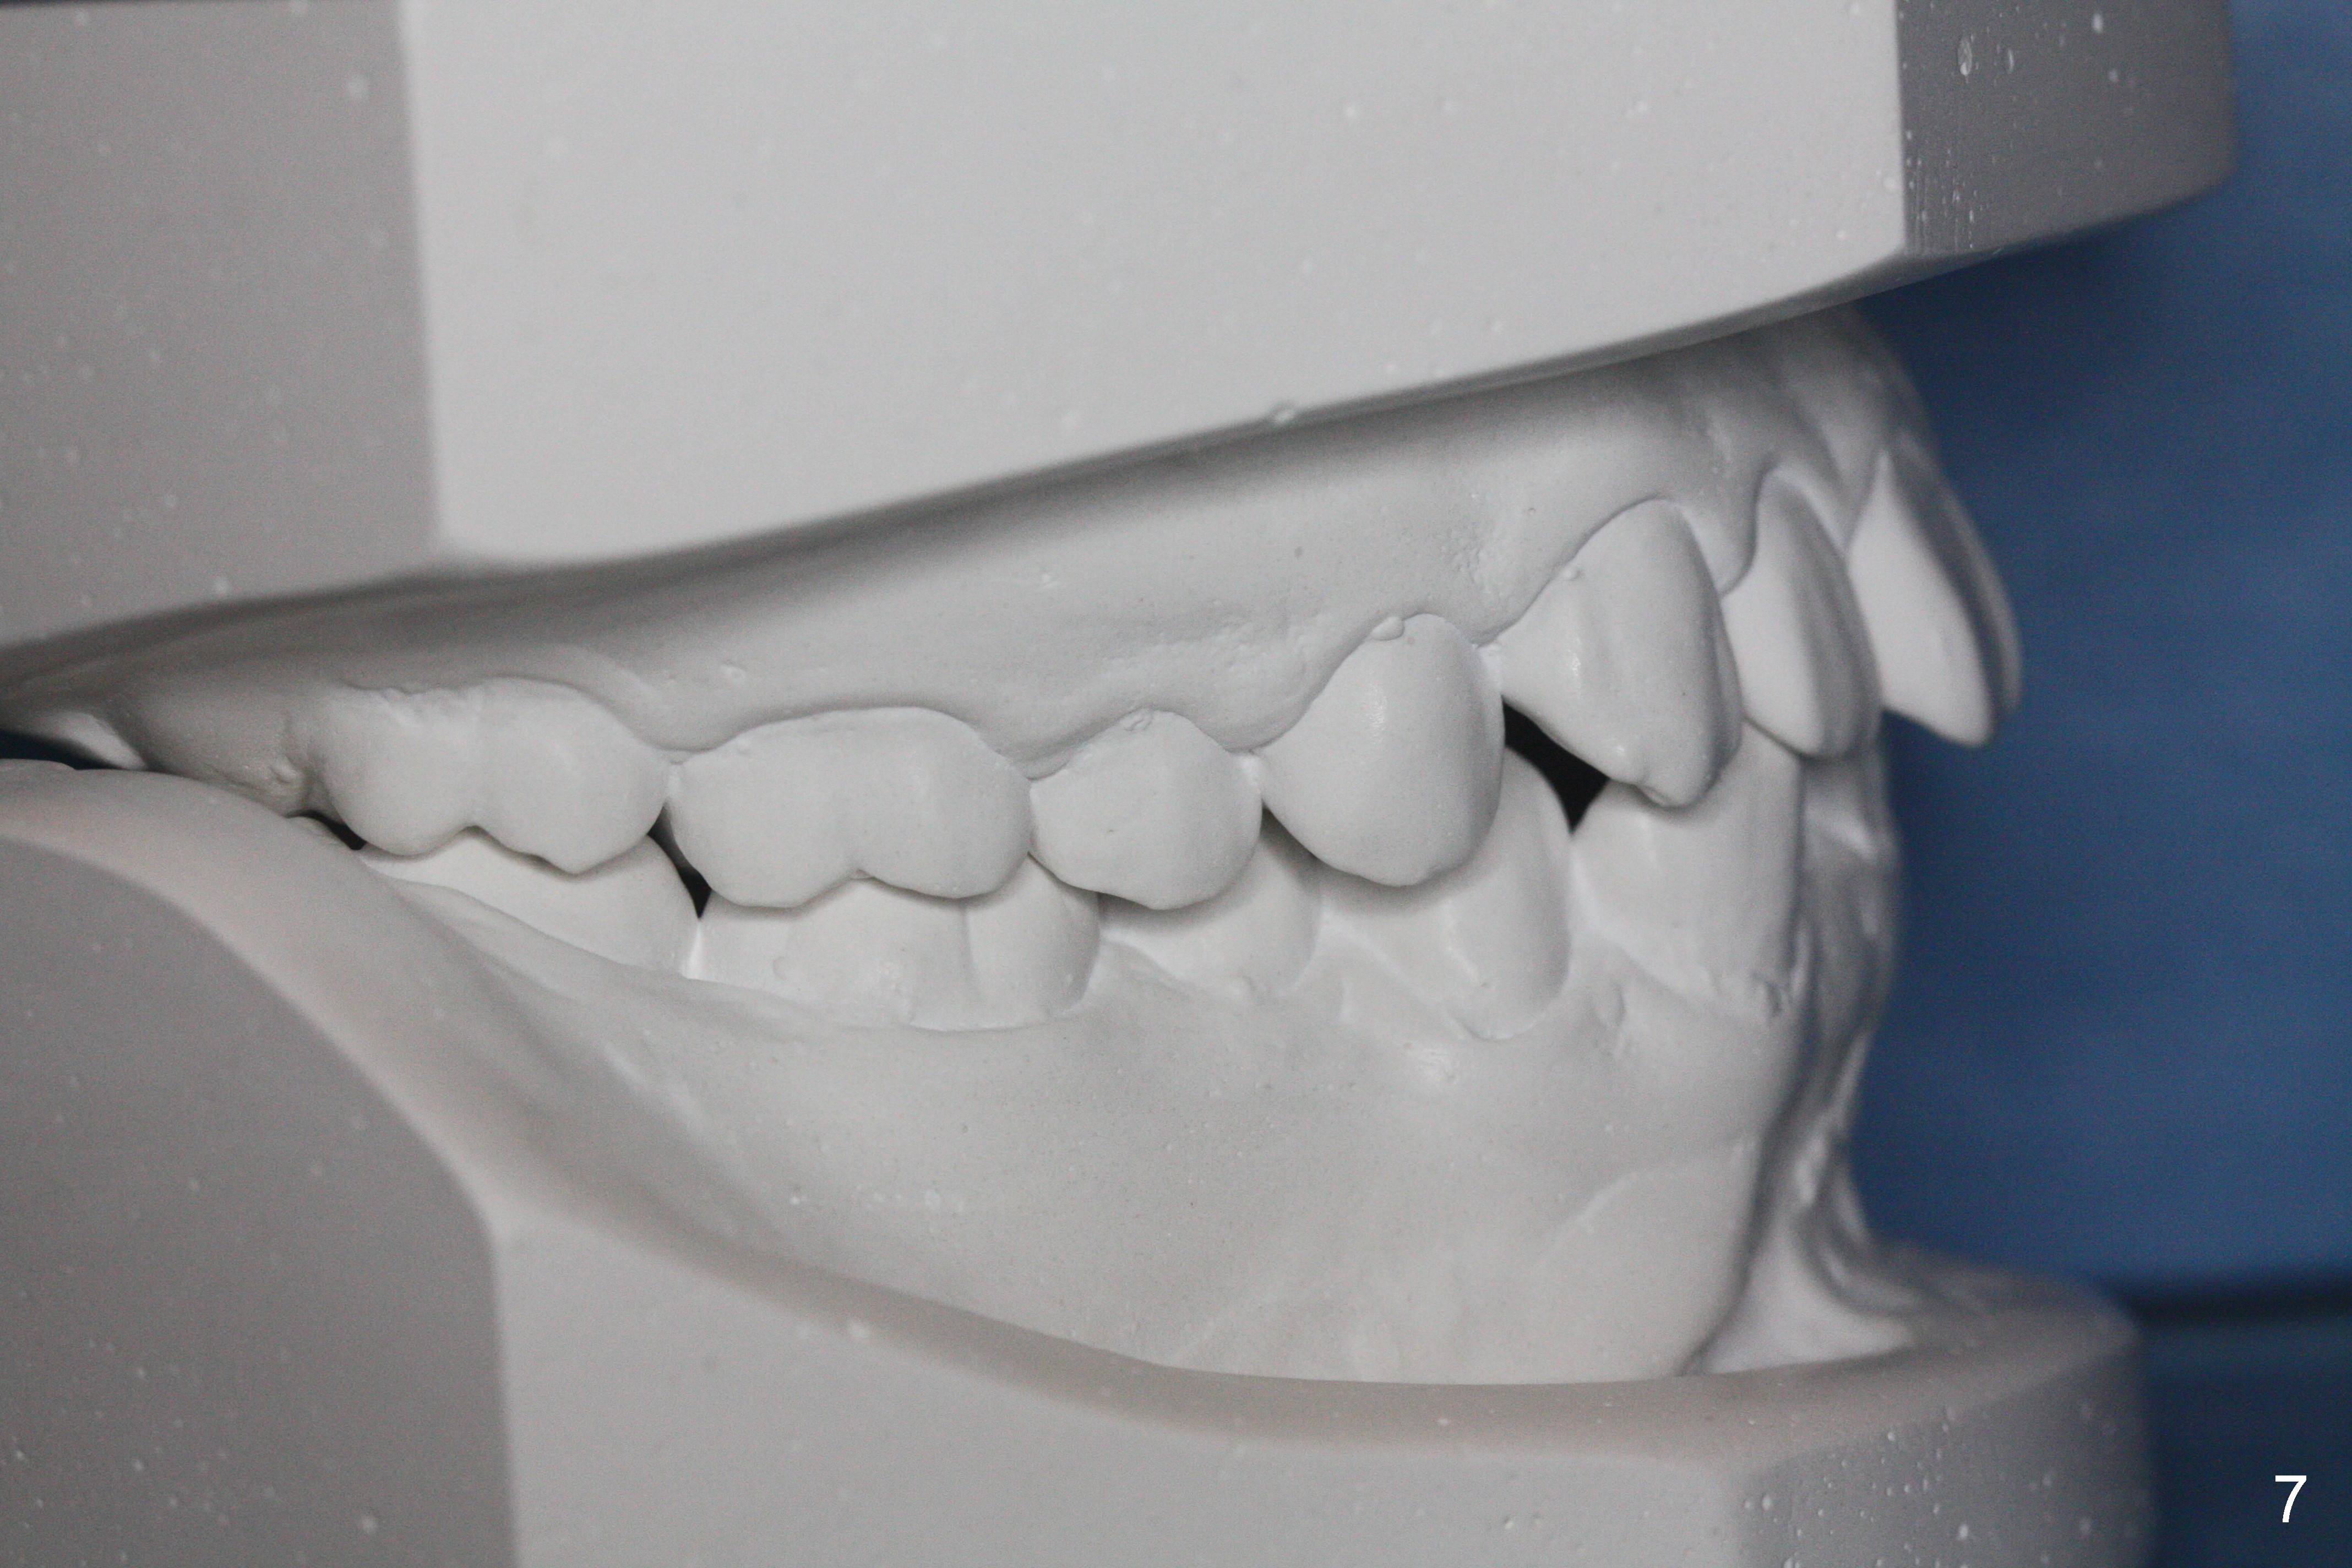

A 15-year-old man wants to improve the facial appearance.

Xin Wei, DDS, PhD, MS 1st edition 02/27/2017, last revision 09/09/2018